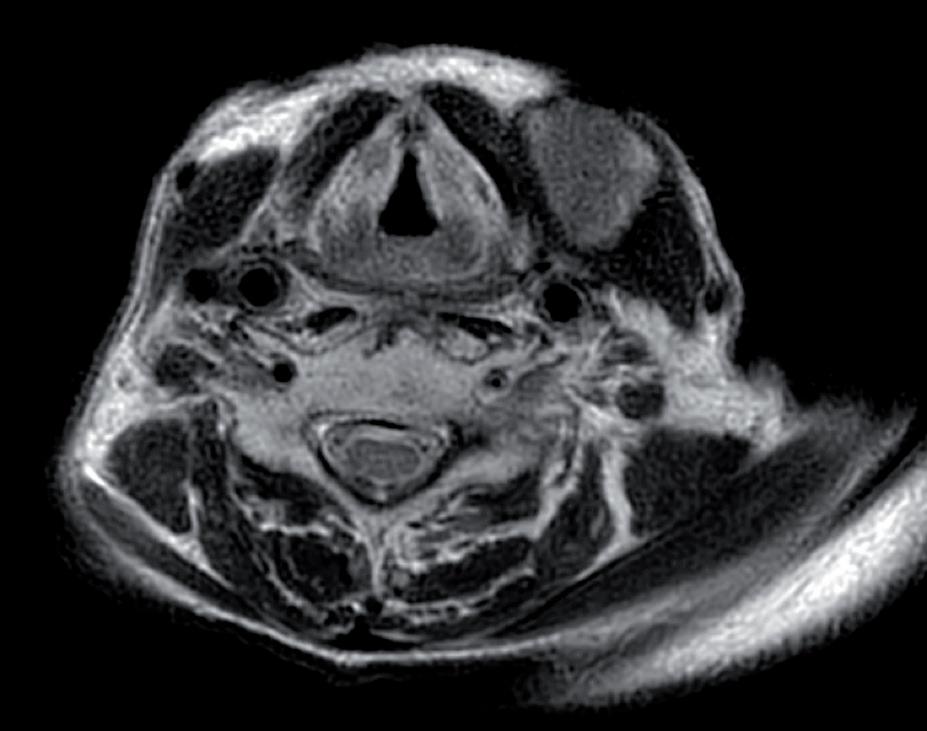

Agosto 2021 PET total body con FDG: “ipercaptazione orofaringea e linfonodale laterocervicale bilaterale” (figure 1 e 2).

Figura 2. PET di esordio che mostra la principale sede di malattia a livello linfonodale laterocervicale sinistro.